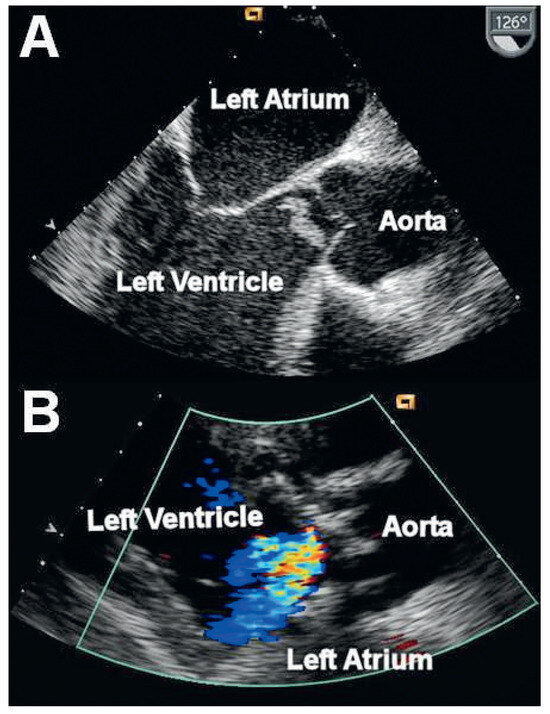

A patient with Morbus Behçet was admitted with severe symptomatic aortic regurgitation caused by aortitis that mimicked infective endocarditis. After aortic valve replacement and antibiotic treatment, regurgitation and systemic inflammation recurred....